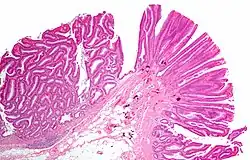

Tubulovillous adenoma (tubular component – left of image, villous component – right of image). H&E stain.

Tubulovillous adenoma

Tubulovillous adenoma, TVA are considered to have a higher risk of becoming malignant (cancerous) than tubular adenomas.[9]